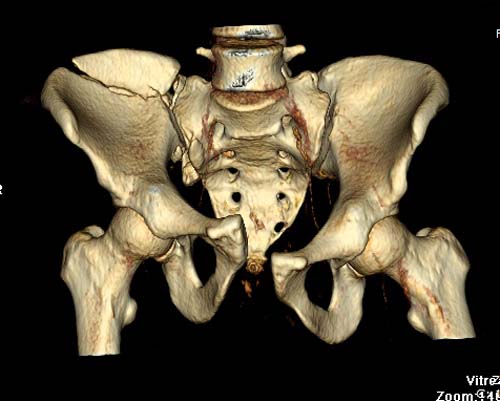

КТ, при детальном рассмотрении виден перелом задних отделов крыла подвздошной кости

KT